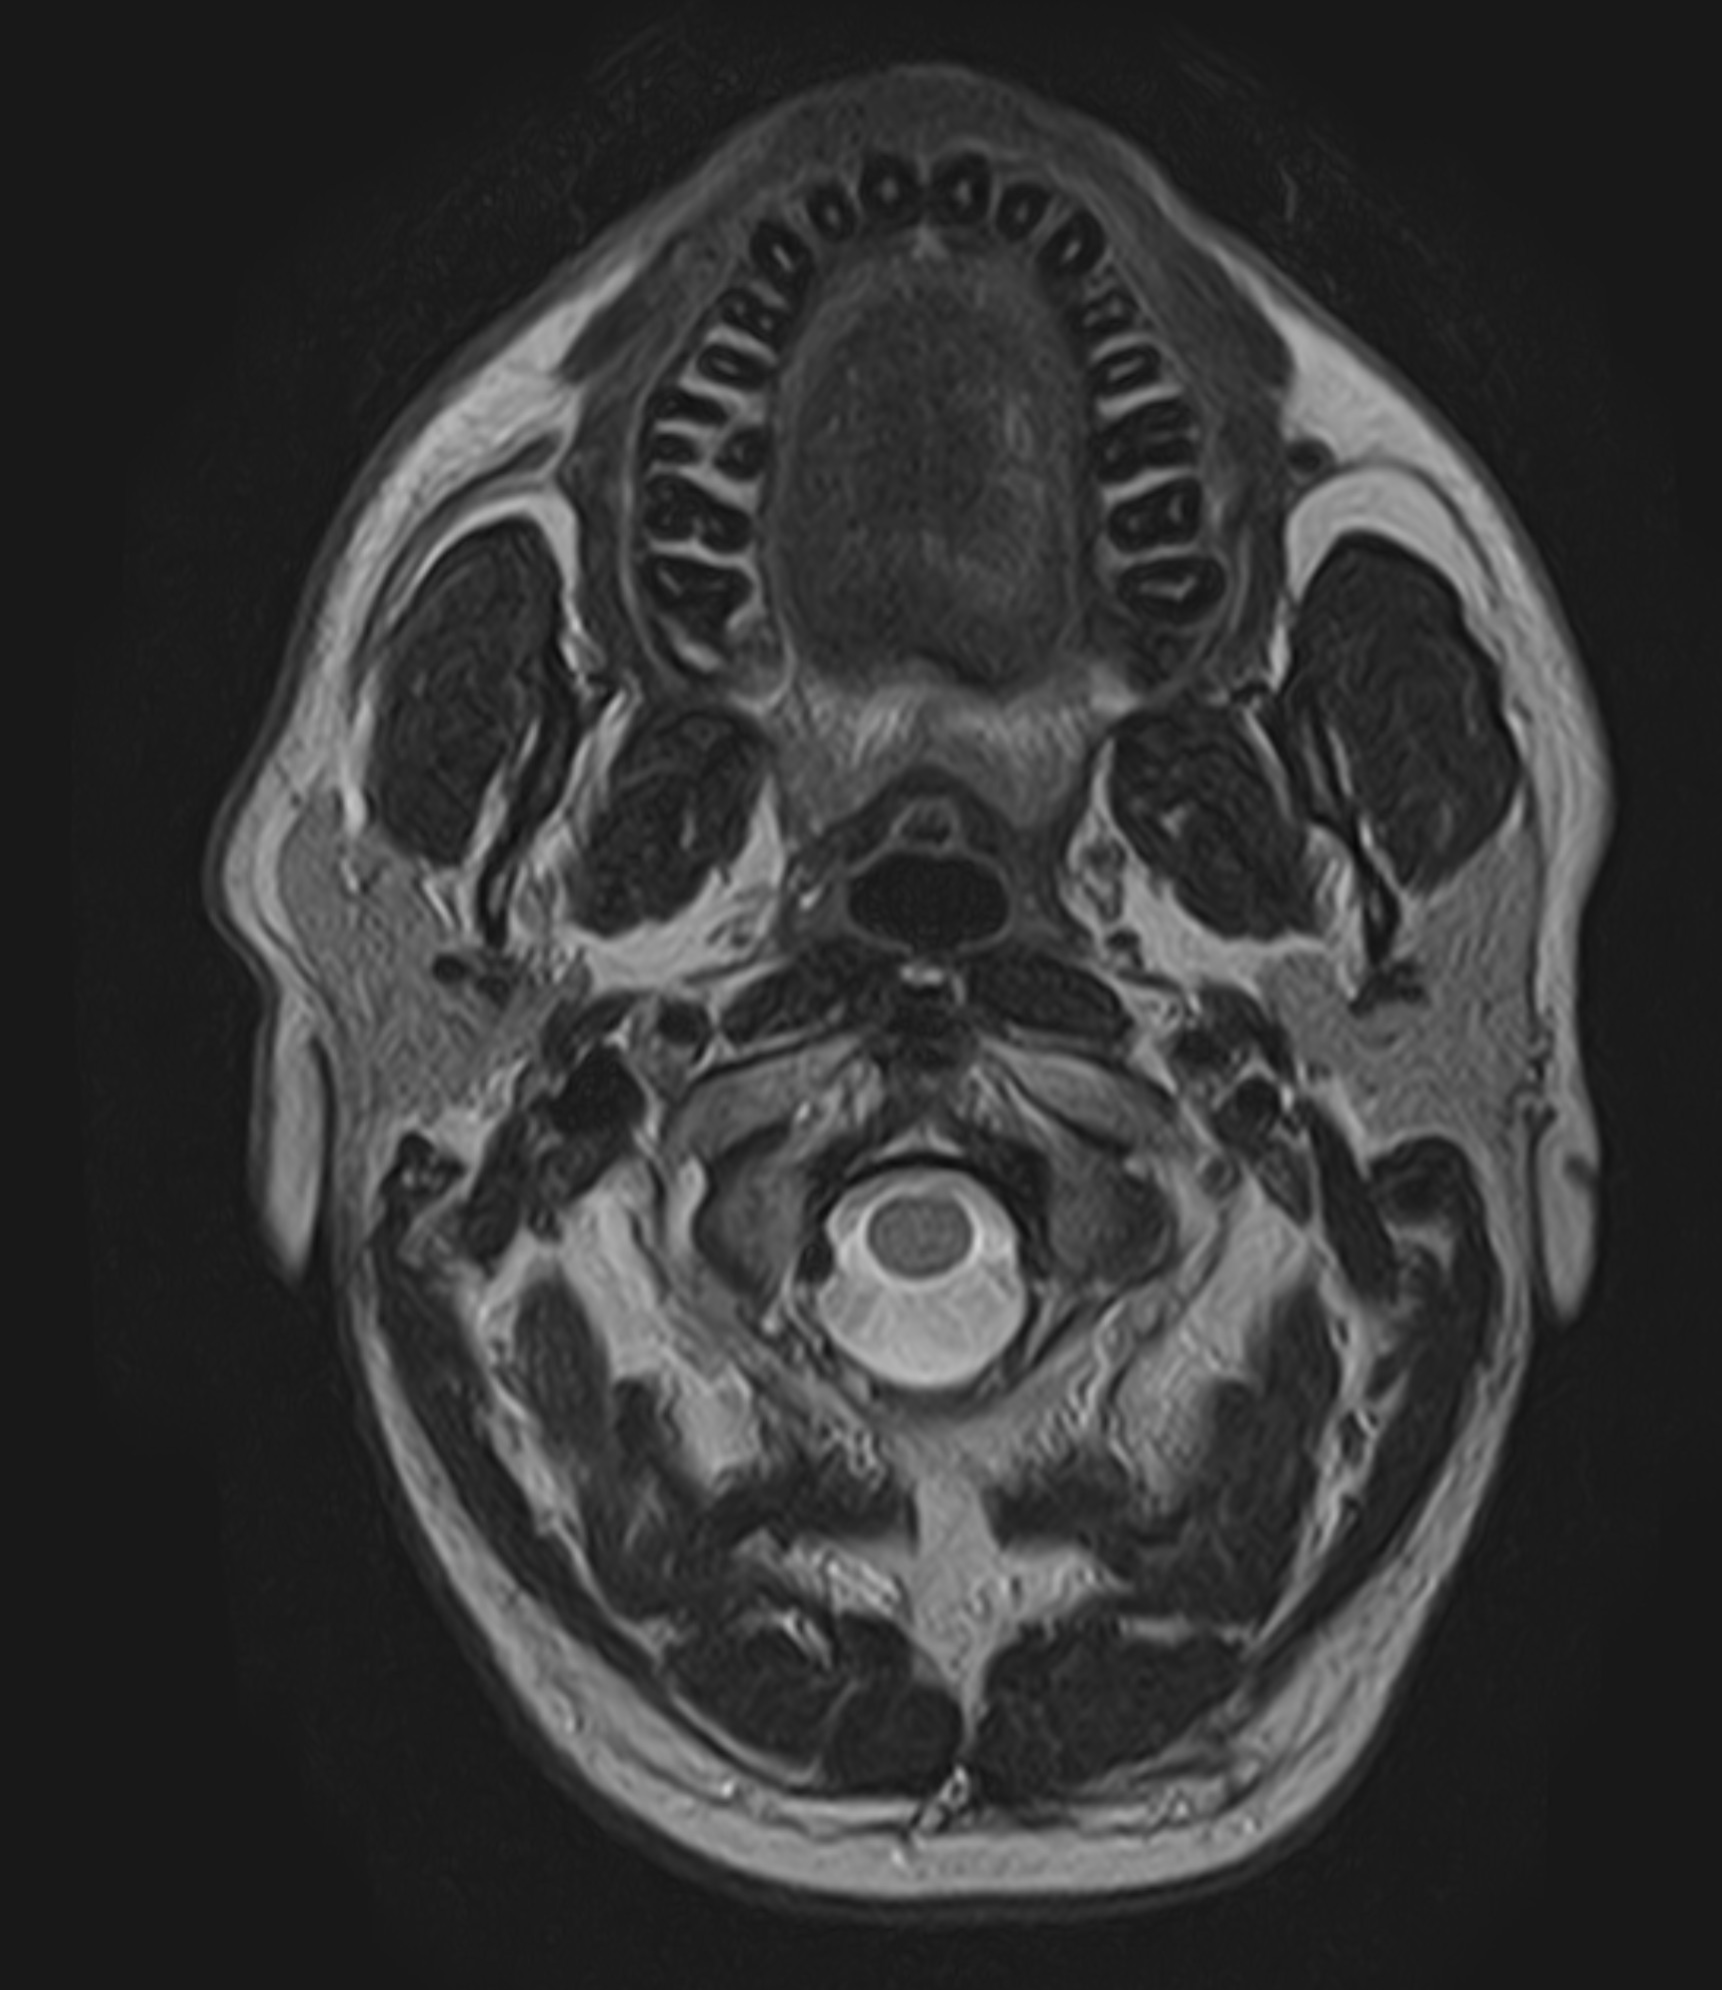

Undersökningen ger mycket högupplösta och detaljerade bilder av innerörats snäckformade gångar (cochlea), båggångarna (balansorganet), hörselgången samt hörsel- och balansnervens förlopp från innerörat till hjärnstammen. MR används bland annat vid misstanke om tumör på hörselnerven, inflammationer, infektioner eller medfödda missbildningar i innerörat.

MR Acusticus är den medicinska benämningen för MR Öron och avser en magnetkameraundersökning med särskilt fokus på hörsel- och balansnerven (acusticusnerven, nervus vestibulocochlearis). Undersökningen används framför allt för att upptäcka eller följa upp akustikusneurinom, numera kallat vestibularisschwannom. Detta är en godartad tumör som vanligen utgår från balansnerven (vestibularis) och kan ge symtom som ensidig hörselnedsättning, tinnitus eller återkommande balansrubbningar.

Det är viktigt att känna till att MR Acusticus och MR Öron i grunden är samma undersökning. Skillnaden ligger i den medicinska frågeställningen på remissen och i den information som anges i anamnesen. Detta styr radiologens fokus och vilka områden som granskas extra noggrant vid bildanalysen. Vid misstanke om tumör riktas särskild uppmärksamhet mot hörselnervens förlopp och dess relation till hjärnstammen. Vid misstänkt inneröresjukdom ligger fokus istället på innerörats strukturer.